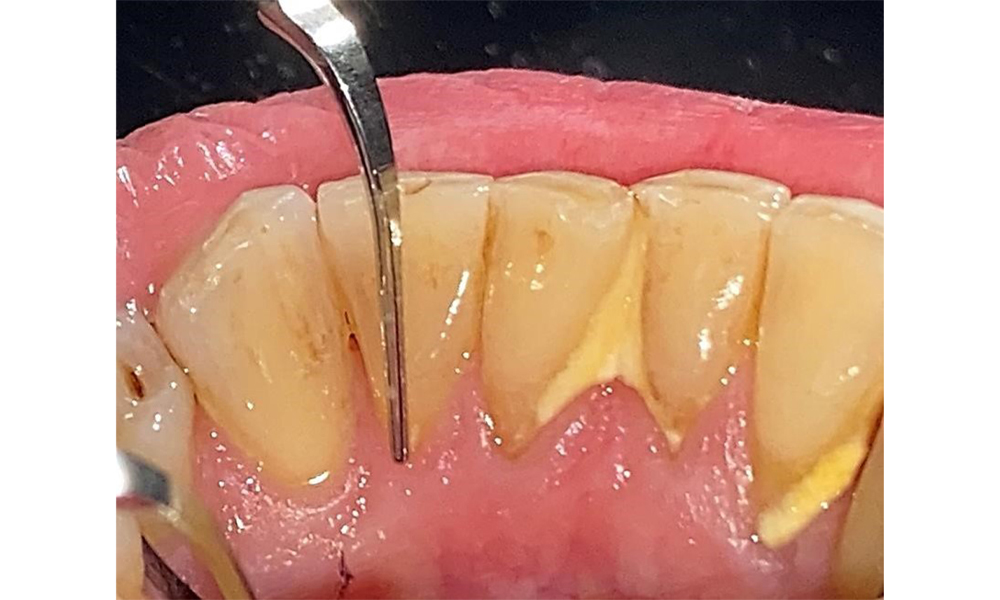

Пациентът има пълно съзъбие с 28 зъба, което включва амалгамни и композитни пломби в областта на моларите и премоларите. На зъб 14 има видима клинична маргинална празнина. Зъб 27 има адекватна златна инкрустация. Налице са и генерализирани атриции и абразии. (фиг. 2, фиг. 3, фиг. 4, фиг. 5, фиг. 6)

Пациентът е с пародонтит II стадий, степен В (5). Клиничните дълбочини на сондиране от 1 до 3 mm са във физиологичния диапазон. Локализирани дълбочини на сондиране от 5 mm са наблюдавани медиопалатинално на 17 и 27. Налице са генерализирани рецесии от 1 до 3 mm с частична загуба на интердентални папили (фиг. 2, фиг. 3, фиг. 4)

Пациентът използва интердентални четки и електрическа четка за зъби и спазва добра орална хигиена у дома. Редовната мотивация и повторното обучение са задължителни поради риск от прогресия, особено по отношение на почистването на междузъбните пространства, тъй като в тези области е установена повишена дълбочина на сондиране. В лингвалната област на долната челюст има локализиран зъбен камък и мека плака и те трябва да бъдат показани на пациента. Може да се наложи да се провери и коригира размерът на интерденталните четки. Въз основа на наличието на открити коренови повърхности се препоръчва мека приставка на четката, за да се предотвратят клиновидни дефекти. Трябва да се използва паста за зъби с ниска абразивна стойност.

Няма ограничения по отношение на избора на методи за измерване. Редовната супрагингивална и субгингивална инструментация е от съществено значение за предотвратяване на прогресията на заболяването поради вече съществуващия пародонтит и високия риск от рецидив. От общомедицинска гледна точка няма ограничения върху избора на инструменти за механично отстраняване на биофилм и отстраняването трябва да се извършва според нуждите. Твърдата и минерализирана плака, като зъбен камък и конкременти, трябва да се отстранява с помощта на ръчни инструменти или ултразвукови скалери (фиг. 9) (8, 9).